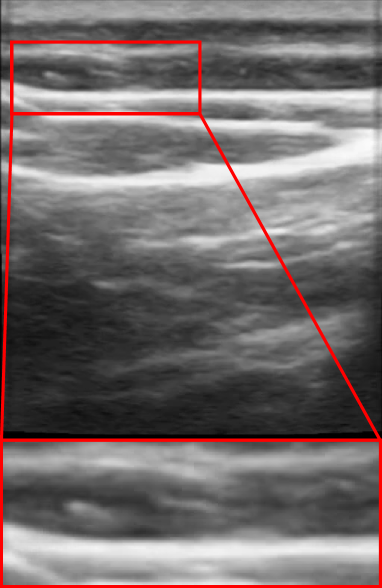

There are a few challenges common across all these learned digital methods: the need for high-quality diverse datasets that capture intricate details like tissue interface locations in high detail, accurately modeling transparent and reflective surfaces, specular surface rendering, and delineating boundaries between different tissues. We qualitatively show some NeRF artifacts that appear when Ultra-NeRF is adopted (Wysocki et al., 2024) on ultrasound images in the wild in Figure 2. These challenges are common across all medical NeRF-based methods. In contrast, our approach, NeRF-US, produces artifact-free reconstructions with minor details that are accurately reconstructed, as shown in Figure 3.

We present the qualitative results of novel view synthesis in Figure 7. We particularly show that other approaches tend to reconstruct ultrasound scenes with severe geometric artifacts. The rendered ultrasound scenes are blurry or torn apart along the moving trajectory. We particularly also notice that other approaches especially Ultra-NeRF (Wysocki et al., 2024) produce reconstructions where tissue borders and separation are not captured properly due to a lot of uncertainty in these areas by all previous approaches. We also demonstrate some of these issues in Figure 8. Our approach particularly alleviates these issues with the reconstruction of 3D ultrasound representations.